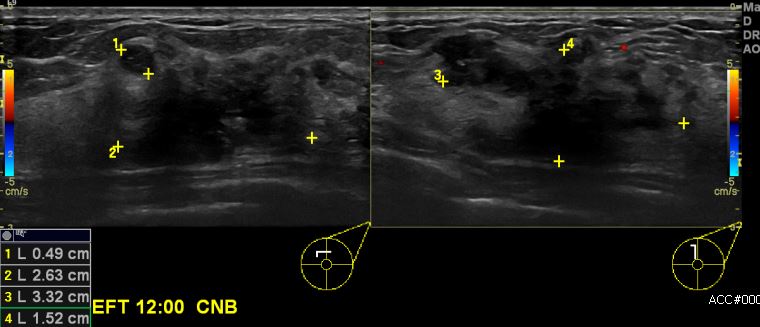

상기환자 건강검진상 이상소견으로 내원하신 50대 여성분으로 좌측 12시 방향에

의심스러운 혹 조직검사 시행하여 좌측 침윤성 유관암 진단 되었습니다.